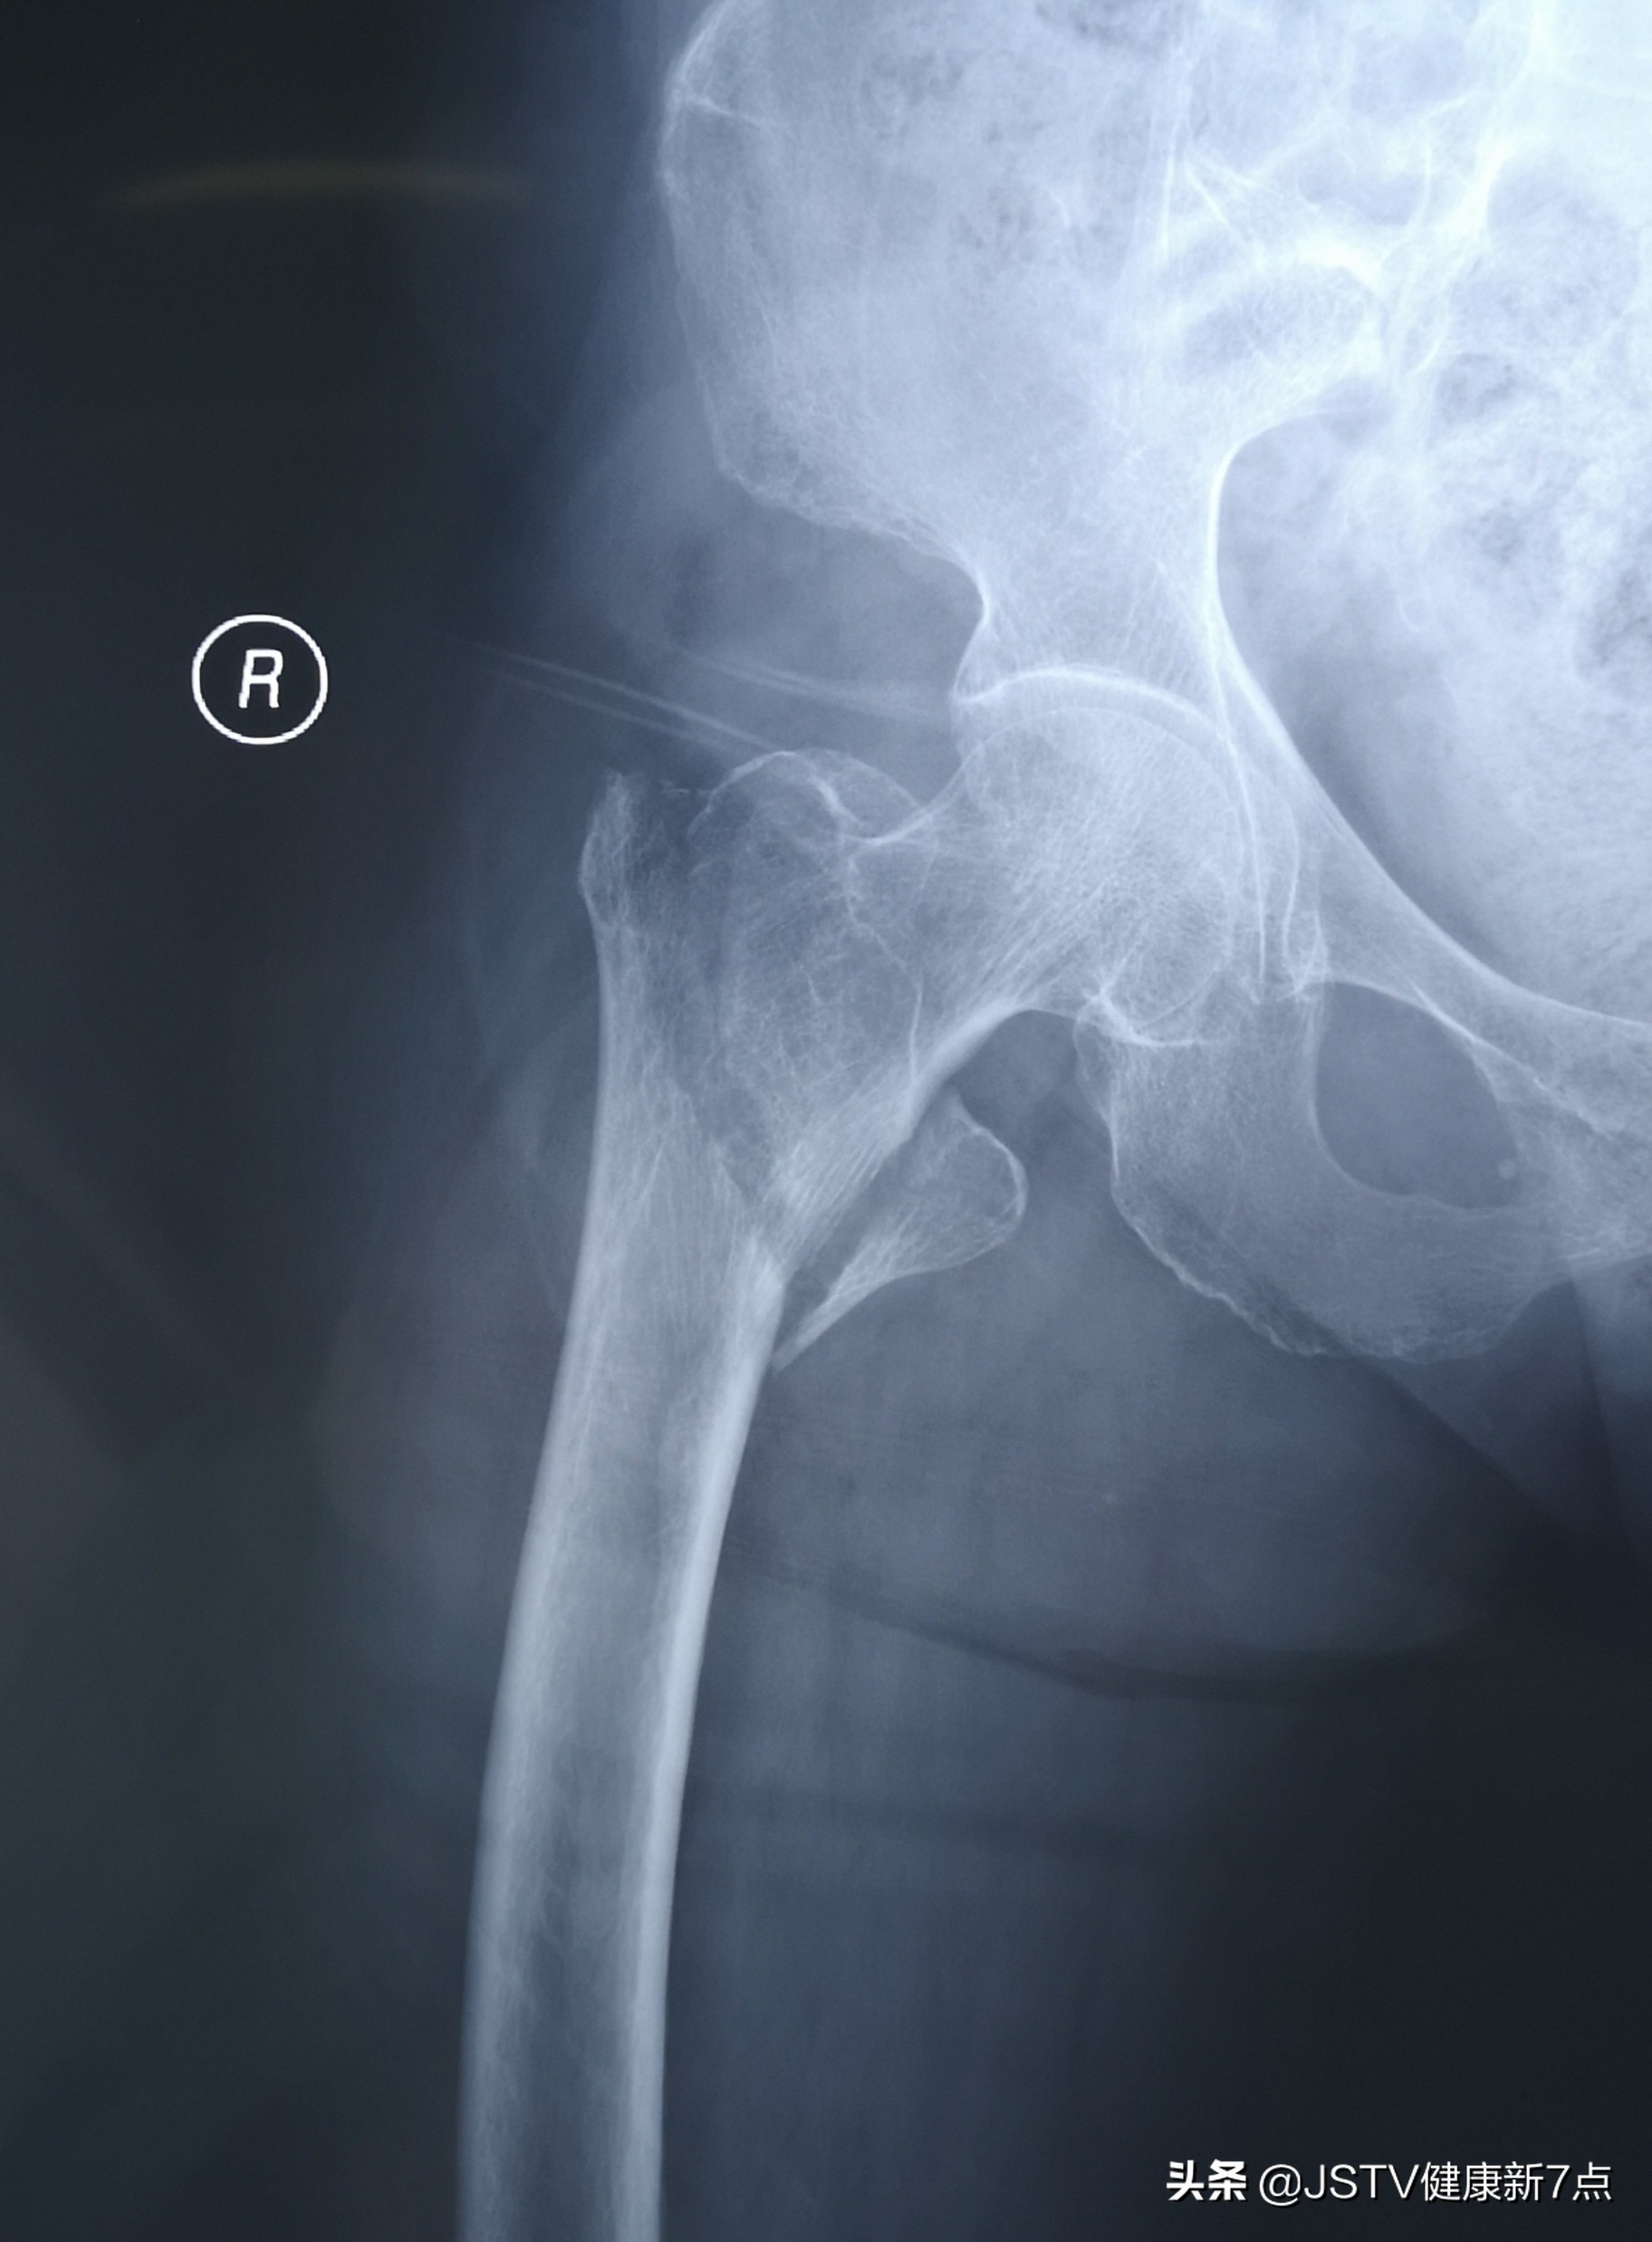

拍摄X线片后,梁主任发现李奶奶右大腿股骨骨折,诊断为右股骨粗隆间骨折。在仔细查询病史后得知,李奶奶患有高血压、糖尿病、冠心病,常年服用药物控制这些基础疾病,血压、血糖控制尚可,然而李奶奶毕竟是高龄老人,再加上有基础疾病,手术的难度相当大。

患者股骨骨折的影像资料